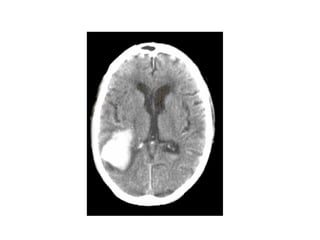

Signes précoces d’AVC ischémique (sylvien)

Signes précoces d’AVCischémique (sylvien)